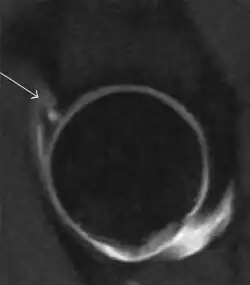

Synovial chondromatosis can be confidently diagnosed by X-ray when calcified cartilaginous chondromas are seen. However, other synovial proliferative processes, such as pigmented villonodular synovitis, require MRI for accurate diagnosis, although noncalcified synovitis can be suspected in radiographs by indirect signs, such as soft tissue swelling and/or erosions in the femoral head, femoral neck, or acetabulum (Figure 7).[1]

Figure 7:

-

Axial CT image of pigmented villonodular synovitis eroding the posterior cortex of the femoral neck.[1] -

Sagittal T2* gradient echo image showing a posterior soft tissue mass with hypointense areas secondary to hemosiderin deposition.[1] -

In synovial proliferative disorders, MRI demonstrates synovial hypertrophy. In the case of PVNS, characteristic foci of low signal intensity related to hemosiderin deposition are better seen on gradient echo T2* images (Figure 7). In the case of synovial osteochondromatosis, the synovial hypertrophy is accompanied by intermediate signal cartilaginous loose bodies and/or low signal calcified loose bodies.[1]